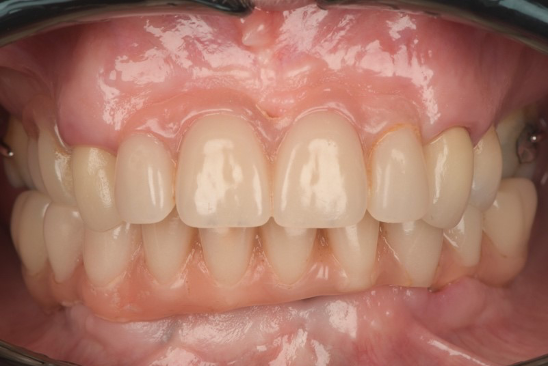

An example of one of the first cases that we did this way is below, including the most recent images of the case.

This illustrates the power of guided surgery and constant improvement.

Here is a more recent case…

Not only have we honed our techniques and are using the better, modern equipment available to us, but our systems and processes allow us to work smarter, not harder.